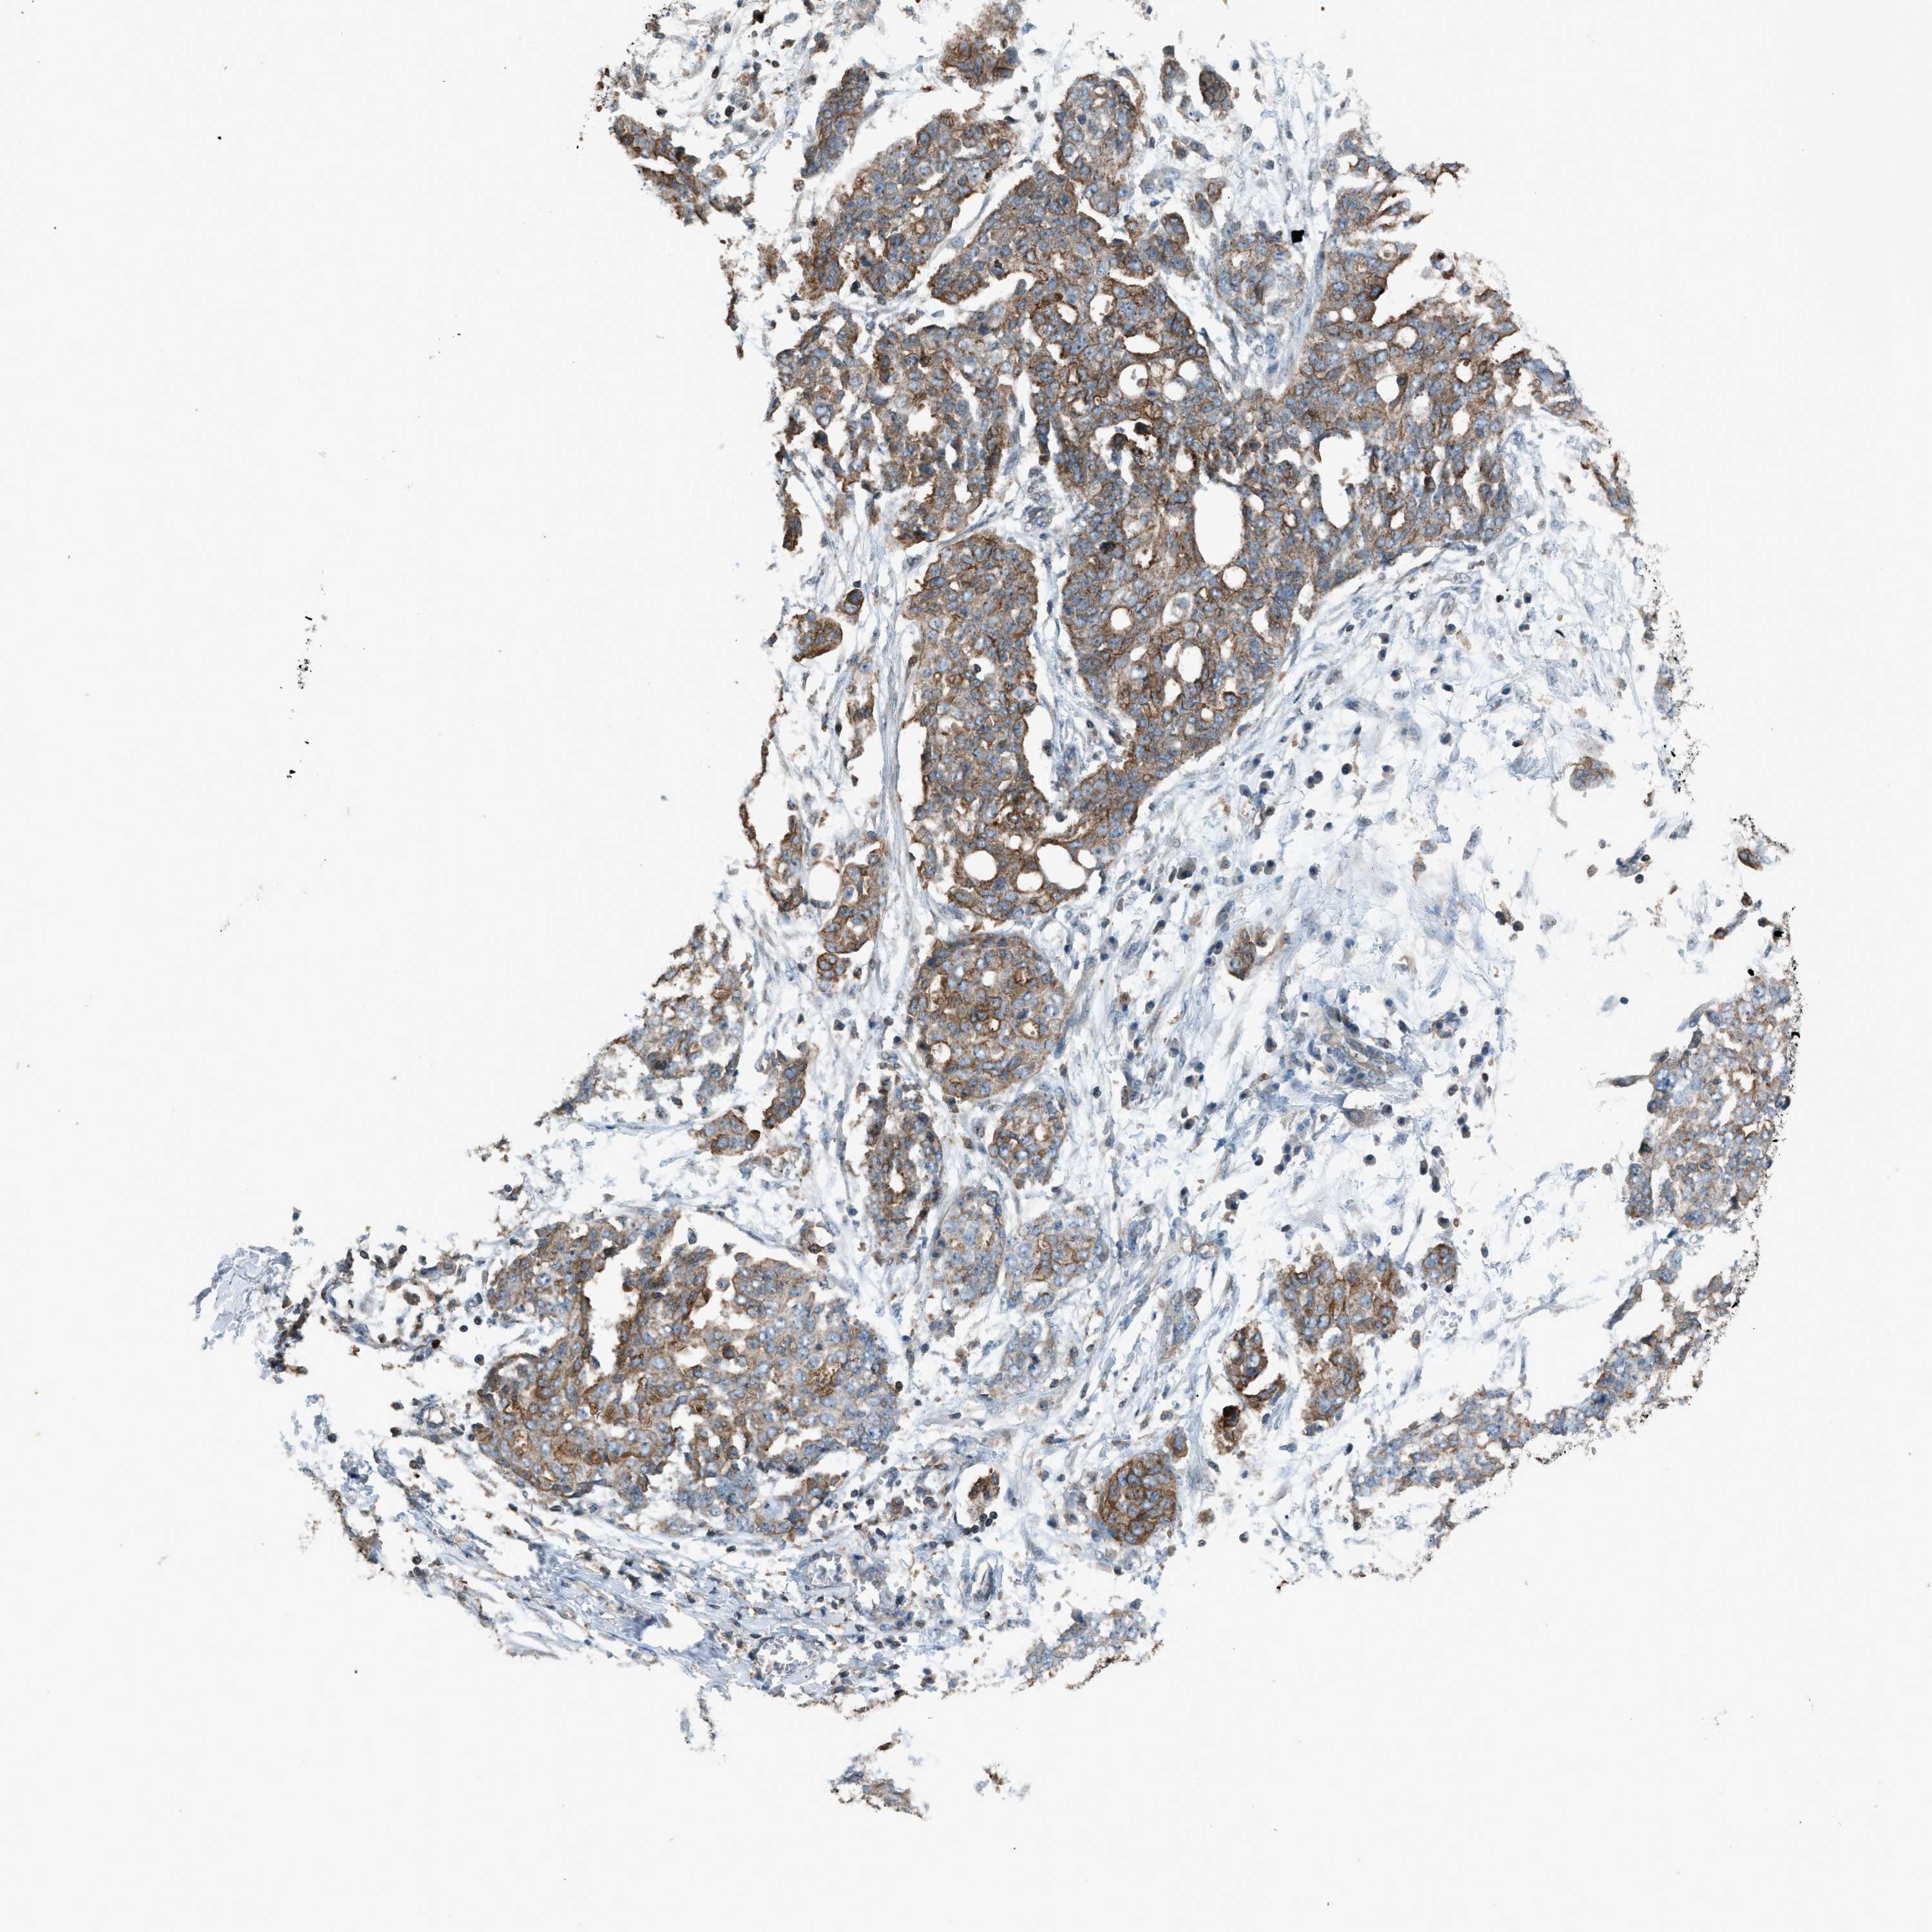

OVARIAN CANCER - Protein expressioni

A mouse-over function shows sample information and annotation data. Click on an image to view it in a full screen mode. Samples can be filtered based on level of antibody staining by selecting one or several of the following categories: high, medium, low and not detected. The assay and annotation is described here.

Note that samples used for immunohistochemistry by the Human Protein Atlas do not correspond to samples in the TCGA dataset.

Antibody stainingi

Antibody staining in the annotated cell types in the current human tissue is reported as not detected, low, medium, or high, based on conventional immunohistochemistry profiling in selected tissues. This score is based on the combination of the staining intensity and fraction of stained cells.

Each image is clickable and will lead to virtual microscopy that enables deeper exploration of all samples and also displays staining intensity scores, fraction scores and subcellular localization as well as patient and tissue information for each sample.

Antibody HPA015323

Antibody HPA015810

Carcinoma, endometroid

Cystadenocarcinoma, serous, NOS

Cystadenocarcinoma, mucinous, NOS

Carcinoma, NOS